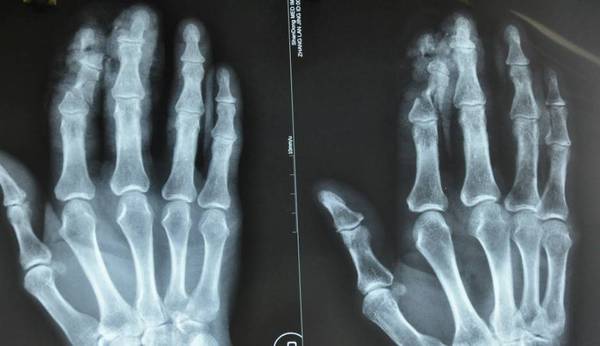

周六夜班收了9个病人,手术室4台显微镜同时使用了,外边还有一个病人需要再植。